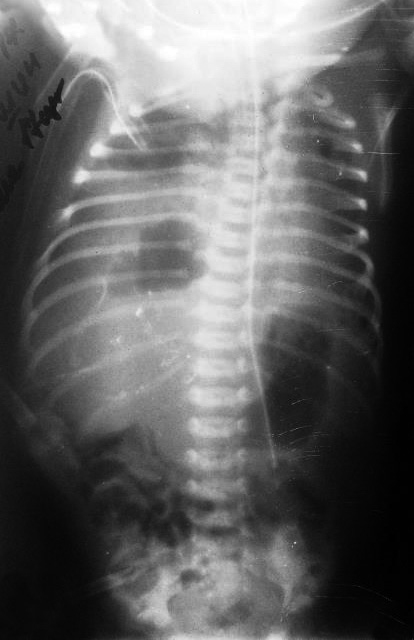

На 13-е сут после операции отмечалась отрицательная респираторная динамика – усиление втяжения грудной клетки, ослабление дыхания слева. По рентгенограмме – подозрение на левостороннюю диафрагмальную грыжу (рис. 8). Ребенок переведен на ИВЛ, начата интенсивная терапия в режиме предоперационной подготовки. По эхокардиограмме – декстракардия, расширение правых отделов сердца. Отмечались постоянные срыгивания при кормлении, проведена декомпрессия желудка, «голодная пауза». На рентгенографии ЖКТ с проходящим контрастом – перемещение части желудка и петель кишечника в передние отделы левой грудной полости, затемнение левых легочных полей (рис. 9).

Рис. 8. Рентгенограмма органов грудной клетки. Признаки левосторонней диафрагмальной грыжи.

Рис. 9. Рентгеноконтрастное исследование с пассажем контраста для подтверждения левосторонней диафрагмальной грыжи. Перемещение части желудка и петель кишечника в передние отделы левой грудной полости, затемнение левых

Ребенок прооперирован 02.06 – лапаротомия в левом подреберье, проведена пластика левого купола диафрагмы искусственной твердой мозговой оболочкой. Послеоперационный период протекал без хирургических осложнений. На рентгенограмме грудной клетки на 4-е сут после операции – легкие пневматизированы, корни за тенью средостения, которая расширена за счет вилочковой железы; диафрагма с четким контуром, кишечник пневматизирован, деформация 2, 3, 4 ребер слева. Ребенок переведен в отделение плановой хирургии на 11-е послеоперационные сутки, откуда через 13 дней выписан домой под наблюдение участкового педиатра и хирурга с рекомендациями.